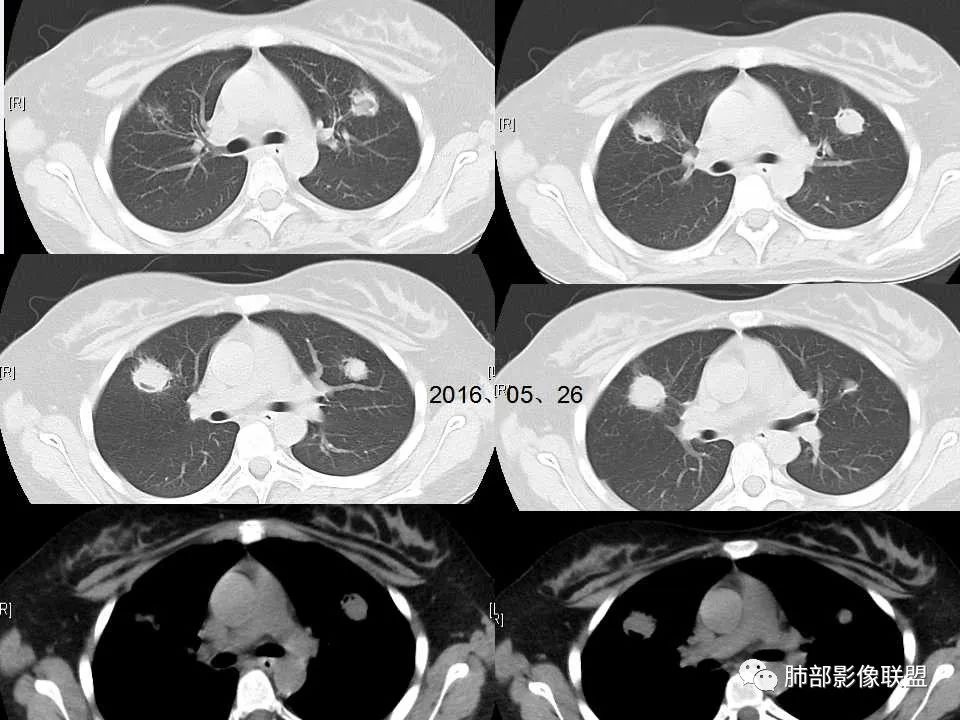

侵袭性肺曲霉病影像分型及表现

5、血管侵袭性肺曲霉病的常见影像表现:①“晕征”;②空气新月征;③胸膜下楔形影-肺梗死;

6、寄生性曲霉病影像学表现:常表现为原有空腔性病灶中的曲菌球。 医学百科网 | YxBaike.Com